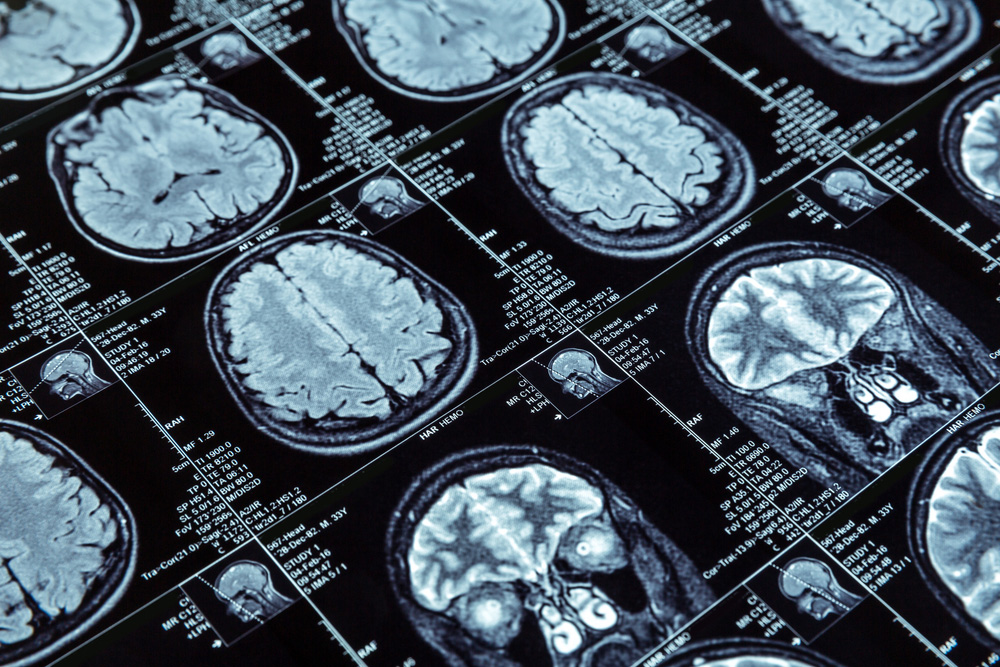

Expert treatment for neurological conditions to help you maintain independence and quality of life.

Learn Your RiskIf you or a loved one has a condition affecting the brain, spine, nerves or muscles, count on the Riverside Brain & Spine Institute to help restore your quality of life.

Riverside’s neurosurgeons are specially trained in some of the most advanced, minimally invasive techniques and technologies. What’s more, patients who suffer a stroke or brain or spinal cord injuries don’t need to be transported by ambulance or helicopter to distant medical facilities for care, saving precious time. Our dedicated team ensures comprehensive, expert care right here at Riverside.